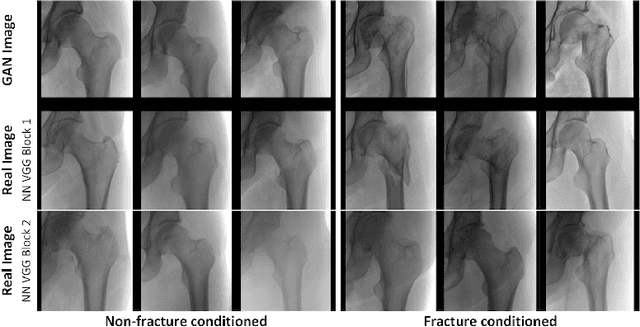

Abstract:Medical students and radiology trainees typically view thousands of images in order to "train their eye" to detect the subtle visual patterns necessary for diagnosis. Nevertheless, infrastructural and legal constraints often make it difficult to access and quickly query an abundance of images with a user-specified feature set. In this paper, we use a conditional generative adversarial network (GAN) to synthesize $1024\times1024$ pixel pelvic radiographs that can be queried with conditioning on fracture status. We demonstrate that the conditional GAN learns features that distinguish fractures from non-fractures by training a convolutional neural network exclusively on images sampled from the GAN and achieving an AUC of $>0.95$ on a held-out set of real images. We conduct additional analysis of the images sampled from the GAN and describe ongoing work to validate educational efficacy.